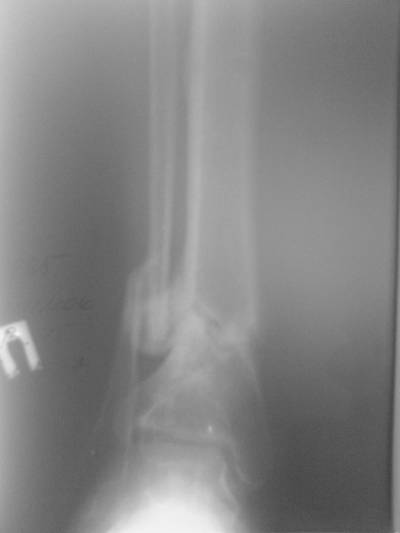

Больной случайно попал в поле зрения с переломом шейки бедра. Страдает

хр. алкоголизмом. От когда-то предложенного удлиннения голени пациент

отказался. После снятия аппарата он пропал как с белых яблонь дым ...

Укорочение конечности 3 см. Передвигался без дополнительной опоры с

"нарощенной" подошвой на правой обуви. Ограничение тыльного и

подошвенного сгибания - умеренные (всего примерно 50%, не измерял).

Вложение не в текстовом формате было извлечено…

Имя     : Tibi1.jpg

Тип     : image/jpeg

Размер  : 23214 байтов

Описание: отсутствует

Url     : http://weborto.net:8080/pipermail/ortho/attachments/20070606/3107b3f1/attachment-0006.jpg